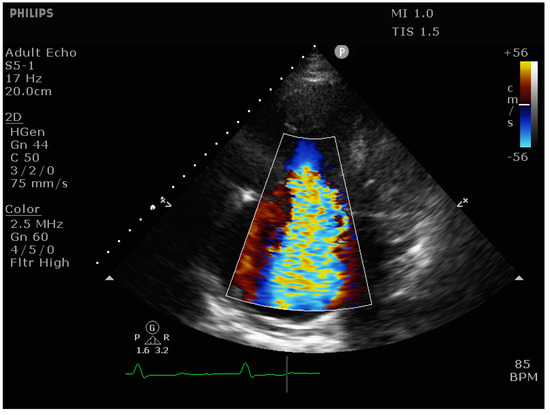

- Vena contracta (VC) width: The width of the regurgitant jet is measured as it leaves the regurgitant orifice. It is best imaged perpendicular to the valve plane, e.g., in the apical 4-chamber view, using CFD with a Nyquist limit of 50–60 cm/s. The VC width corresponds to the width of the narrowest portion of the jet (the “neck), with values > 7 mm suggestive of severe TR.

- Proximal isovelocity surface area (PISA): [46] With significant TR, there is a flow acceleration proximal to the regurgitant valve orifice. This proximal flow convergence occurs along concentric hemispheres and can be visualized using CFD with an adequately set Nyquist limit (15–40 cm/s) to maximize delineation of the flow acceleration. The radius of the PISA correlates with TR severity, with values > 9 mm suggestive of severe TR.